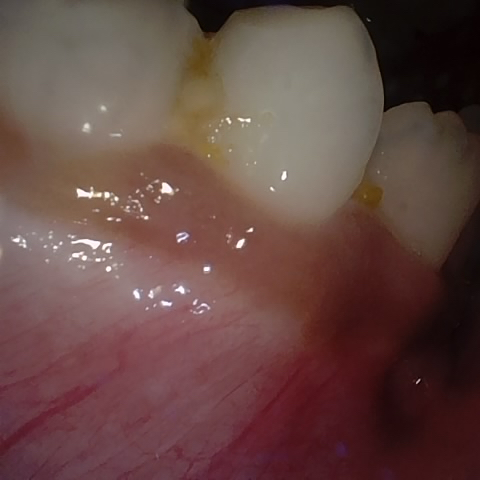

Image 245 / 255

NHD27230

Annotated as "Good"

Original Image Rendering Image